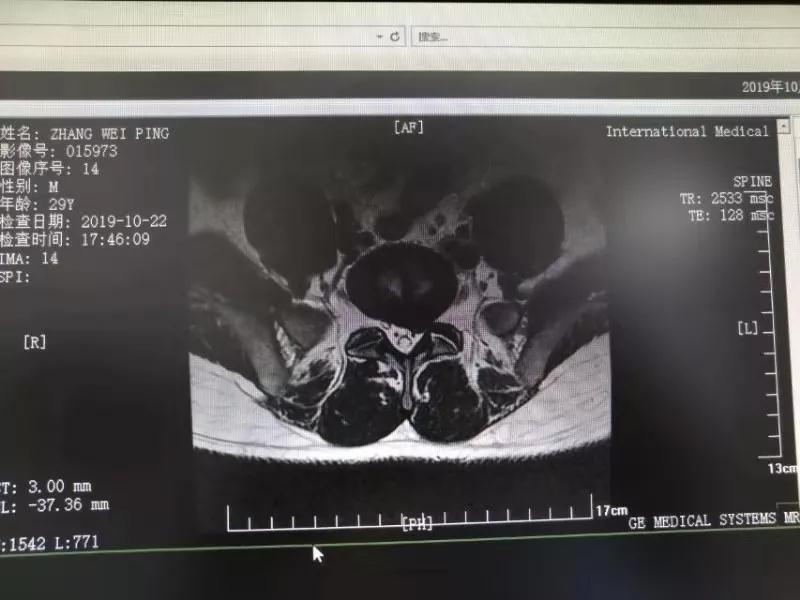

10月25日,29歲的患者小張了解到西安國際醫(yī)學(xué)中心骨科醫(yī)院專家云集,一大早便在家人的陪同下,來到西安國際醫(yī)學(xué)中心骨科醫(yī)院就診?!拔已闯掷m(xù)2年多,最近感冒后腰痛癥狀明顯加重了。”小張面露苦楚,因?yàn)殚L期腰痛、左下肢放射性疼痛,她晚上睡覺不能平躺,經(jīng)常疼得睡不著,需要口服止痛藥物才能有所緩解。走路走不了多遠(yuǎn)就開始腿抽的疼,嚴(yán)重影響到工作和生活。

結(jié)合患者的檢查以及年齡情況,王自立副院長推薦讓專門研究椎間孔鏡技術(shù)王雄勛主任給小張做微創(chuàng)的椎間孔鏡手術(shù)。該手術(shù)創(chuàng)傷很小,不影響脊柱的穩(wěn)定性,尤其適合于椎間盤突出的年輕患者,懷著對骨科醫(yī)院專家的信任,小張與家人商議后,接受手術(shù)治療。